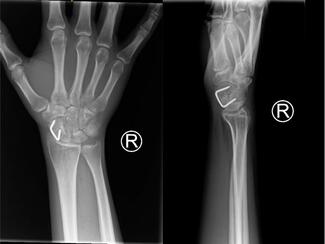

This case is a 32-year-old male with refractory AED secondary to a crush injury in June 2019. He initially presented to an outside hospital before meeting with our plastic surgery team in January 2022, with his operation performed in March 2022. Following his original trauma, he required open suprapubic tube placement and multiple cystoscopies for a urethral injury as well as open fixation of a pelvic fracture. Recovery was complicated by a membranous urethral stricture requiring a posterior urethroplasty in November 2019. At the time of our assessment, the patient was voiding spontaneously but was unable to achieve an erection. The patient denied a history of smoking. Workup with urology included a pelvic angiogram showing patent bilateral iliac arteries and bilateral inferior epigastric arteries but complete occlusion of the distal left internal pudendal artery with no filling of the left dorsal or cavernosal penile artery branches as well as complete occlusion of the distal right penile artery. Our plan was for circumcision and revascularization of the penis utilizing the right DIEA with anastomosis to DPV in conjunction with urology. Computed tomography angiogram of the abdomen and pelvis was performed to assess the donor vessels preoperatively.